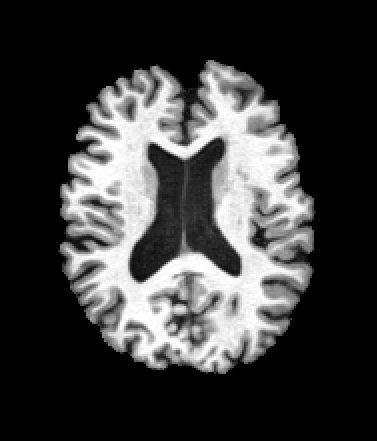

A trained MetaVoxel model can be unconditionally sampled by drawing Gaussian or categorical noise for each variable at timestep , and iteratively apply the denoising network until reaching . Unlike conventional diffusion models that focus solely on image generation, MetaVoxel can generate coherent synthetic patient profiles from the joint distribution , as shown in Figure 2.

| Age: 64.0 | Age: 53.8 | Age: 70.9 | Age: 76.9 |

| Sex: Male | Sex: Female | Sex: Female | Sex: Male |

![]() |

| Age: 80.9 | Age: 77.7 | Age: 73.2 | Age: 84.6 |

| Sex: Male | Sex: Female | Sex: Female | Sex: Female |